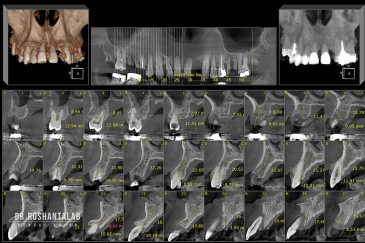

🔸 ایمپلنت دیجیتال و ساخت روکش دیجیتال